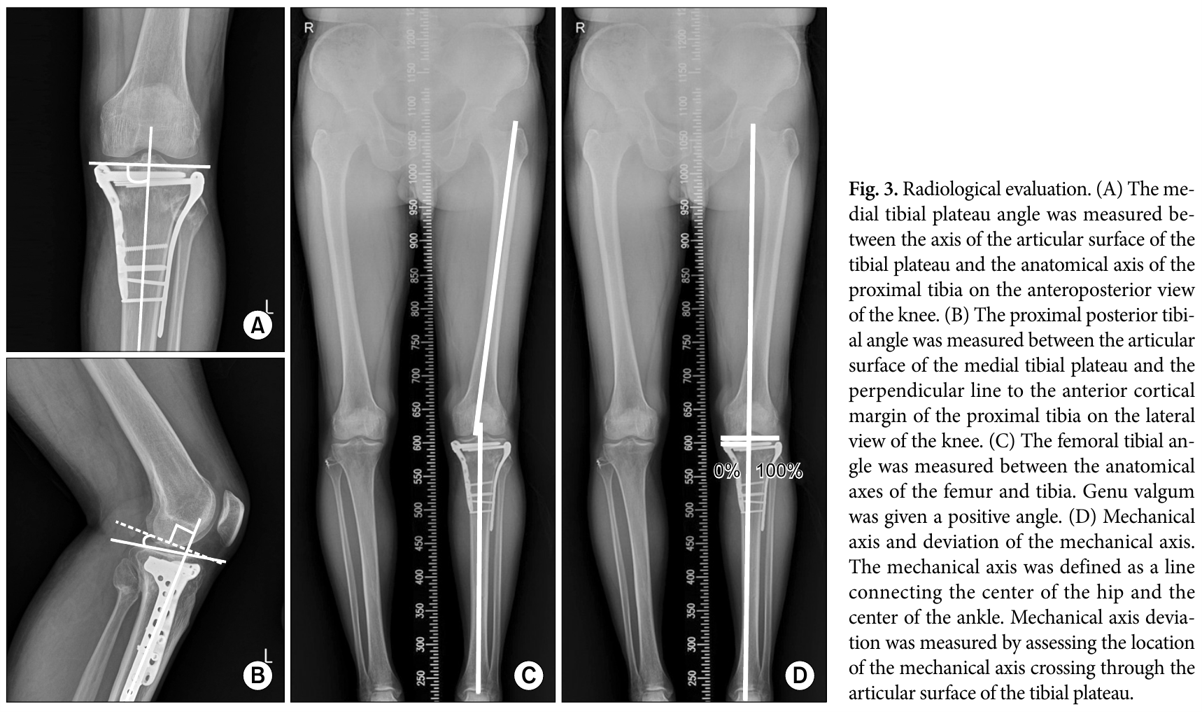

손 교수님이 가끔 전공의들에게 불같이 화를 내실 때가 있었습니다. 그중에 하나가 경골 고원부 골절에 관한 처치였습니다. 만약 외고정술을 하기로 결정이 났다면, CT촬영을 외고정술을 하고 난 뒤에 진행하라고 늘 말씀하셨습니다. 왜냐하면 외고정술을 하고 무릎 주위 위아래로 약간 견인을 하면 뼈에 붙어 있는 인대와 같은 연부조직들이 원래 위치로 가려하기 때문에 뼛조각들이 원래 상태에 가깝게 정복이 되기 때문이었습니다. 이 개념이 전문 용어로는 ligamentotaxis라고 합니다. (사진 1)

traction_pre_post.png 사진 1. 외고정장치 적용 전(위) 후(아래) CT 영상 비교: 견인을 통한 정복을 보여주는 증례입니다.

수술을 잘해서 뼈를 잘 맞추면 임상결과가 당연히 좋을 것이라고 예상해 볼 수 있습니다. 저는 여기서 ‘얼마나’ 잘 맞추면 ‘얼마나’ 좋아지는 가에 집중하였습니다. 손 교수님과 결론을 상의하면서 수술 시 건측 (반대쪽) 다리의 각도를 참고해서 최대한 비슷하게 맞출수록 또한 경골의 후방 경사각을 건측과 비슷하게 맞출수록 더 좋은 임상 결과를 얻을 수 있다고 결론을 내렸습니다. (사진 3) 정형외과 임상연구는 ‘얼마나’라는 단어에 집중하면 연구주제가 떠오를 수도 있다고 생각합니다.

KSRR.png 사진 3. 수술의 정밀함을 찾아서: 정확한 각도 복원이 환자의 예후를 좌우합니다.